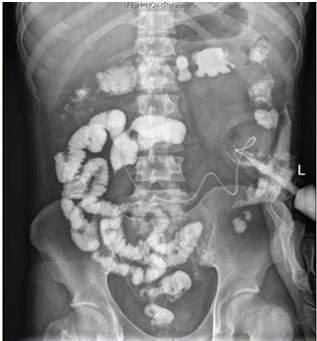

| 图 5 双腔造瘘管造影(2018-3-20):可见造瘘管、结肠各段及直肠通畅,未见对比剂外漏征象。 |

1 资料与方法患者男,30岁,因“腹胀、腹痛6 d,高热1 d”于2017年12月11日由广州南沙区中心医院转诊收入中山大学孙逸仙纪念医院全科医学科。患者本次起病前无明确病因或明显诱因。患者以左上腹轻微胀痛起病,进行性加重。南沙区医院查血常规:白细胞14.27×109/L,血小板50×109/L,中性粒细胞比例74.5%,嗜酸粒细胞1.02×109/L,嗜酸粒细胞比例7.2%。全腹CT+CTA提示:门静脉左右主干及其小分支栓子形成。后在3 d内连续复查血常规,提示血小板进行性下降,由50×109/L相继降至35×109/L、18×109/L;(嗜酸粒细胞计数及比例未能提供),并出现高热(体温39.5℃),因病情危重,遂转诊本院。入院时患者精神疲乏、高热,腹部胀痛难忍,伴有咳嗽。查体:体温38.6℃,心率87次/min,血压102/76 mmHg,指尖血氧饱和度90%~91%。双肺呼吸音粗,双肺均可闻及小水泡音。腹部稍膨隆,叩诊鼓音,左上腹及脐周轻压痛,无反跳痛。听诊肠鸣音减弱,约1~2次/min。当天查血常规示白细胞11.85×109/L,血小板23×109/L,中性粒细胞比例58.1%,嗜酸粒细胞3.5×109/L,嗜酸粒细胞比例29.5%。凝血常规提示:PT 15.9S,PTA 51.1%,PT/R 1.39,Fbg 1.59 g/L,PTINR 1.39,APTT 35.2 s,D-二聚体114.36 mg/L FEU(参考值范围0~0.55 mg/L FEU)。胸部+全腹部CT+CTA示“门静脉主干及左、右支、肠系膜上静脉近端栓子形成;腹主动脉及左侧髂总动脉小附壁血栓;左肺上叶尖后段、左肺上叶下舌段、右肺中叶及双肺下叶炎症;乙状结肠两段节段性管壁增厚,建议排外占位性病变;腹水、盆腔积液,大网膜炎性病变可能性大”。每日复查血常规,发现血小板进行性下降,最低至15×109/L(参考值范围125~350×109/L),嗜酸粒细胞计数及比例进行性升高,分别达到8.07×109/L(参考值范围0.020~0.52×109/L)和51.1%(参考值范围0.4-8.0%)。每日复查凝血常规亦提示凝血指标不断恶化,纤维蛋白原最低降至0.63 g/L。在予禁食、“美平(美罗培南)”抗感染、输注纤维蛋白原及血小板、维护水电解质平衡及营养支持的积极治疗的同时,还积极完善了以下检查寻找病因:①血液系统方面:血浆鱼精蛋白副凝实验:阳性(+);凝血功能实验:PT 15.5S↑,PTA 47.8%↓,PT/R 1.35↑,PTINR 1.36↑,APTT 40.4 s↑,AT-Ⅲ 57.7%↓,F-VII 32.8%↓,F-Ⅷ 68.1%↓,F-X 68.0%↓,F-XII 24.0%↓;纤维蛋白降解产物:381.4 mg/L↑;血栓弹力-血小板图:R时间10.3 min↑;角度18.5度↓;最大血块强度13.2 mm↓;MA(ADP)值5.6 mm↓。骨髓病理学:嗜酸性粒细胞增多(43%),巨核细胞减少(7个)。慢淋/淋巴瘤表型分析:获取和分析细胞数5.0万;粒细胞区百分比82.6%;淋巴细胞区百分比9.4%;单核细胞区百分比2.0%;CD45dim细胞区百分比1.3%;有核红及细胞碎片区域百分比4.6%。ETV6/PDGFRB融合基因、FIP1L1/PDGFRA融合基因(—)。骨髓细胞学病理结果:符合嗜酸细胞增多症;②消化系统检查:大便细菌培养鉴定及药敏提示无志贺、沙门菌生长,有真菌生长;大便难辨梭菌毒素检测(—);粪便找寄生虫、找阿米巴、寄生虫七项均为(—);消化肿瘤系列提示CA-125 244.8 U/mL↑;腹腔穿刺术穿出“血性腹水”,腹水CA-125 1006.0 U/mL↑,腹水找癌细胞(—);复查腹部CT+CTA:乙状结肠两段节段性管壁增厚,建议进一步检查;排外占位性病变;遂行PET-CT:提示全身未见明确恶性征象。行电子结肠镜示:内镜诊断:(1)回肠末段炎症;(2)乙状结肠炎症;(3)内痔。钳取组织送病理,提示:标本①(回肠末端)黏膜组织呈慢性炎,伴糜烂,一些嗜酸性粒细胞浸润(约35个/HPF);②(乙状结肠)黏膜组织呈慢性炎,伴糜烂,个别嗜酸性粒细胞浸润(约4个/HPF)。③风湿免疫系统方面:免疫八项、风湿四项:C反应蛋134.0 mg/L,余未见异常;总IgE 170 IU/mL↑;抗ENA抗体、狼疮两项、血管炎两项、免疫球蛋白G4、抗心磷脂抗体三项均为阴性;④其他感染病原学检查:乙肝、肝炎系列、性病三项、痰找抗酸杆菌、T-spot实验、流行性出血热、登革热抗体、登革热病毒NS1抗原、外斐氏试验、肥达氏试验、痰结核培养、骨髓培养、血液细菌、血液厌氧菌培养均为阴性。经过上述检查,初步考虑“特发性嗜酸性细胞增多症”,于12.15开始予“甲泼尼松龙40 mg静滴, 1次/d”及“低分子肝素0.6 ml皮下注射, 1次/d”抗炎抗凝治疗。患者病情及检验指标有所好转,热退、腹胀减轻,血常规提示血小板升至49 ×109/L,嗜酸粒细胞计数和比例均下降至正常,凝血常规提示D-二聚体降至47.90 mg/L FEU。但12-22患者自行进食多量米饭后突发腹胀痛较前加重,急查血常规提示白细胞升至21×109/L,血小板再次下降至15×109/L,D-二聚体升至97.28 mg/L FEU,全腹CTA提示“门静脉主干及左、右支、肠系膜上静脉近端新发栓子形成”,遂于当日转至ICU予“尿激酶20万U+肝素钠1250 U”溶栓治疗后予“低分子肝素0.6 ml皮下注射, 1次/12 h”序贯抗凝治疗。后患者病情渐渐稳定,至2018-1-18患者在“甲泼尼松龙12 mg口服, 1次/d”及“立伐沙班20 mg口服, 1次/d”的维持治疗下,血小板、嗜酸粒细胞计数及纤维蛋白原均回复正常,D-二聚体下降至3.52 mg/L FEU。但遗憾的是,此时患者再次进食大量米饭,约1 h后突发腹痛、气促,急行胸片+腹平片提示:“双侧膈下游离气体,考虑胃肠道穿孔可能;双下肺少许炎症,少量胸腔积液;腹部多量积气伴肠腔扩张”。遂即送手术室行全麻下“腹腔镜探查+坏死空肠切除+大网膜切除+肠系膜上动脉探查+空回肠双腔造口术”,术后病理提示标本①(大网膜)脂肪组织,部分坏死,合并慢性炎,伴一些中性粒细胞浸润,较多泡沫样组织增生,未见明确血栓,未见恶性改变。②(部分空肠)肠壁组织,部分肠壁全层坏死,合并慢性炎,肉芽组织增生,未见明确血栓,未见恶性改变。免疫组织化学:CD38浆细胞(+)、IgG(+)、IgG4(﹣)。术后继续予“立伐沙班10 mg/d”和“甲泼尼松龙8 mg/d”口服治疗,并于2018.2.4停用“甲泼尼松龙”。2.28复查全腹CTA,仍可见“脾静脉新发血栓,门静脉及肠系膜上静脉血栓较前好转”。3.20行空回肠双腔造瘘管泛影葡胺造影术提示“双腔造瘘管通畅,右中下腹小肠蠕动尚可,结肠各段及直肠通畅,未见对比剂外漏征象”。但患者合并了严重的短肠综合征,致严重低钾低钠血症和继发的代谢性脑病,病情再度转危。继续纠正电解质紊乱、补充营养,最终病情好转后于4.11行“造瘘口回纳修补术”。随访半年,患者仍口服“立伐沙班10 mg/d”抗凝治疗,复查血常规、凝血常规等各项指标均正常,但营养状况较差。